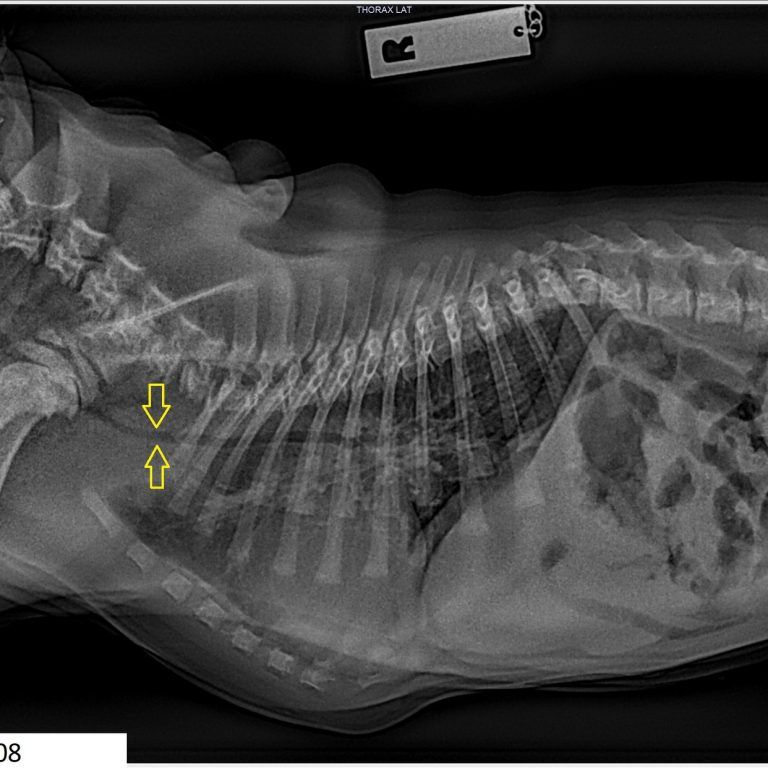

A trachea is considered hypoplastic if it’s ratio is less than 0.16. to 0.20 is a grey area and over 0.20 is excellent. Please see the examples below including Archie who has a normal width of 0.20. Compare the 3 severely hypoplastic ones pictured below.

The three cases discussed/pictured above are extreme. All puppies, all really struggling with bouts of aspiration pneumonia, and all diagnosed with extreme hypoplastic tracheas. Their measurements were 0.07 for two of them and 0.08 for one.